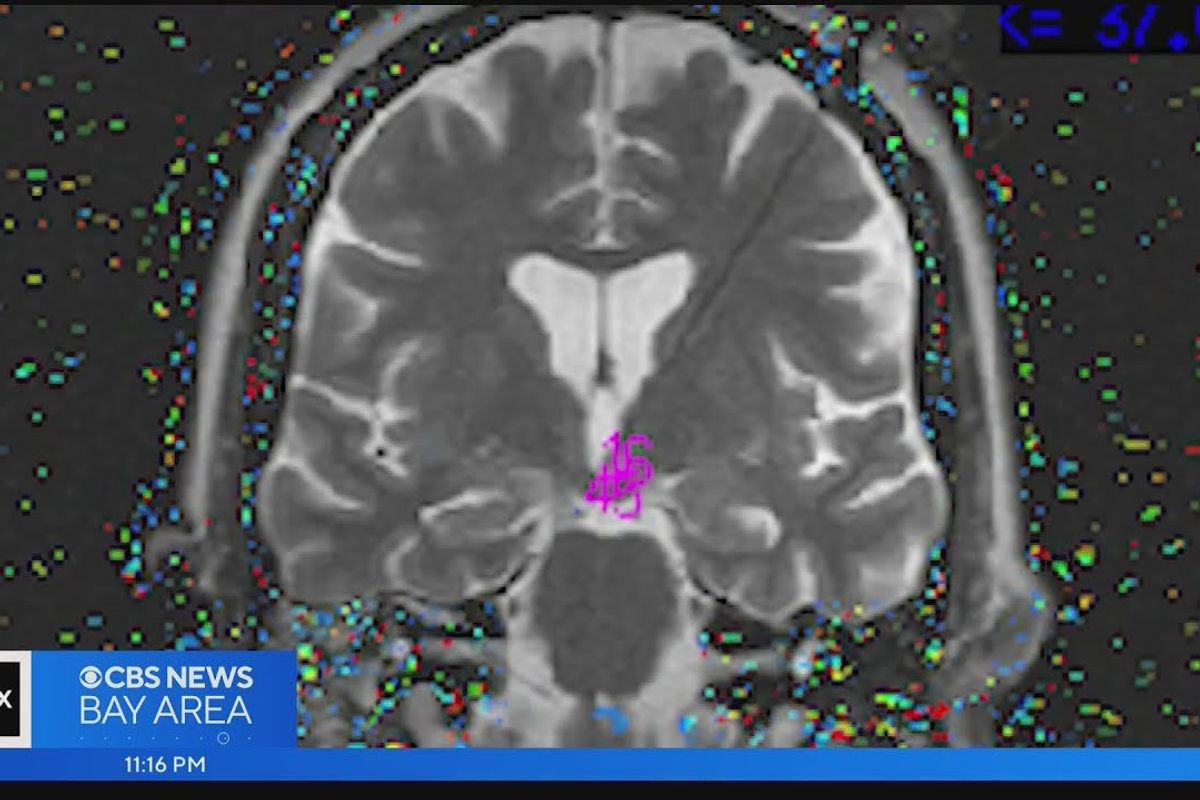

Dr. Paul Garcia, a neurologist who only worked at the hospital a few times a year, was the doctor on call. Upon hearing about Menzies' behaviors during her seizures, he was intrigued and completed an MRI of her brain. It was there that he spotted a small growth on her hypothalamus the size of a lemon seed. The doctor explained the hypothalamus controls a lot, including the nervous system.